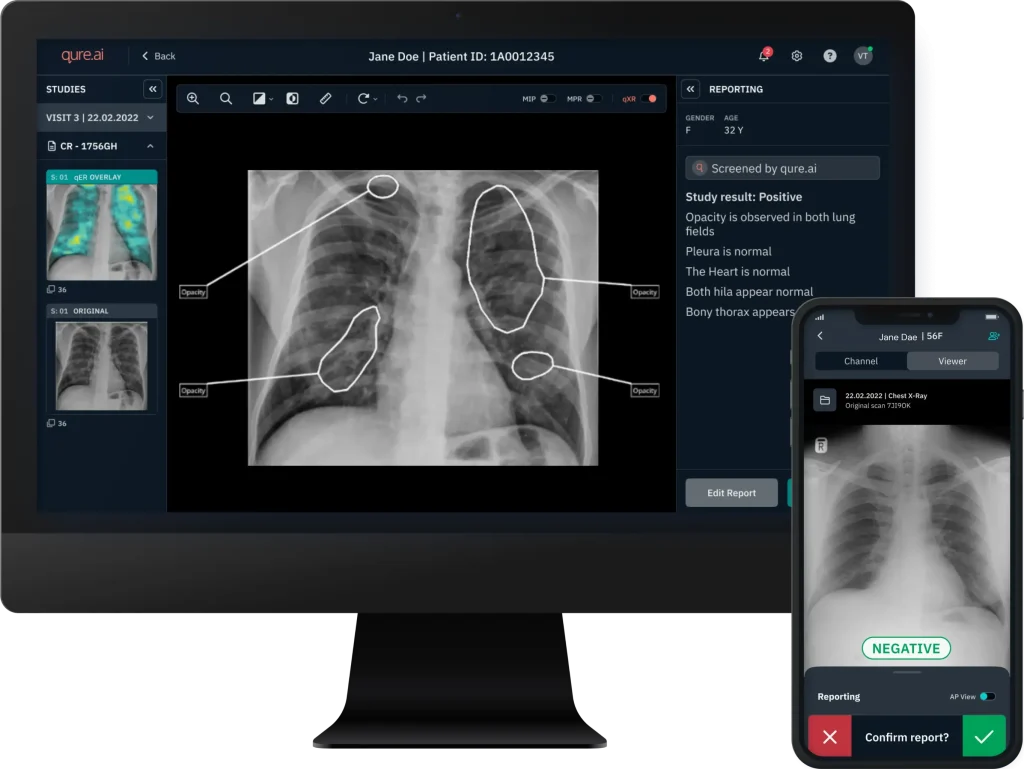

- Cure.AI: Providing AI-driven diagnostic solutions enhancing the speed and accuracy of radiological diagnoses, especially in critical conditions.

- Seamless Integration: AI tools operate within the familiar interface of the Freedom Nano platform, enabling immediate adoption and usability.

Innowave is actively deploying AI algorithms from its partners across hospitals and diagnostic centers in India and Indonesia, bringing cutting-edge tools into mainstream healthcare. AI-assisted diagnostics are being utilized in:

Mass screening programs for tuberculosis (TB) using chest X-rays, improving early detection and public health outcomes.

Rapid interpretation of Head CT scans for trauma patients, facilitating timely triage and emergency care.

Body CT scans, where AI tools assist radiologists in identifying critical findings, improving turnaround times and diagnostic consistency.